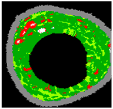

Figure 3.

Clustering by K-means, (a) cluster 1, (b) cluster 2, (c) cluster 3, and (d) cluster 4.

As illustrated in Figure 2 and Figure 3, unsatisfactory segmentation results are obtained in terms of the overlap borders in the VH-IVUS image, so an accurate algorithm should be developed.